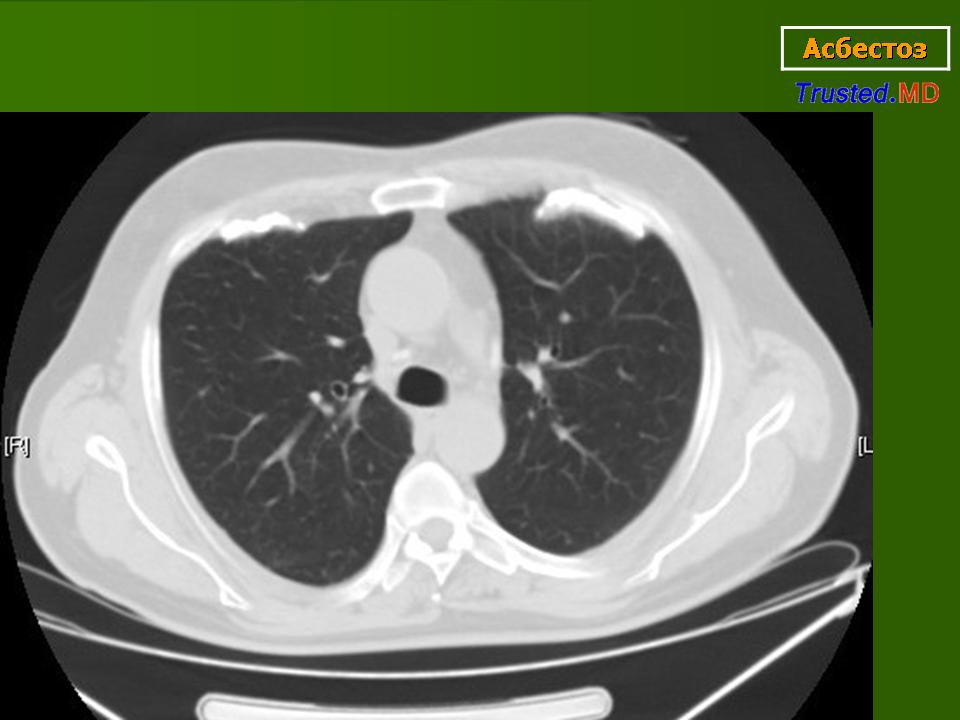

Асбест 2 CTa

Дата: 06/02/2004

Просмотров: 541